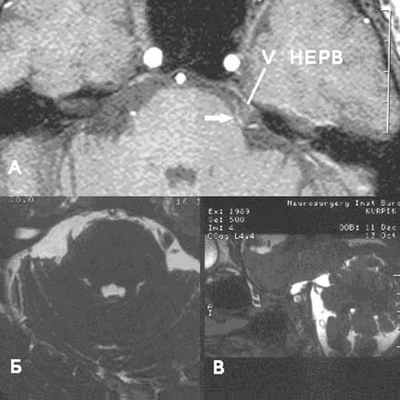

Аксиальный срез (А, Б), сагиттальная проекция (В). Определяется нейроваскулярный конфликт между артерией и тройничным нервом. Компрессия тройничного нерва прилежащей к нему артерией обозначена стрелкой.

У места выхода тройничного нерва из ствола головного мозга (обозначено кругом) определяется крупный артериальный сосуд, компремирующий указанный нерв. На противоположной стороне визуализируется корешок V нерва, на расстоянии от которого проходит аналогичный артериальный сосуд.